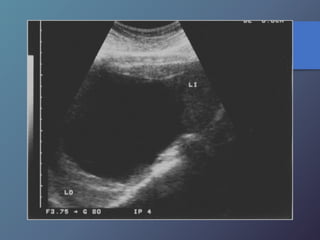

Síndrome de Budd-chiari

• Se caracteriza por la oclusión de las venas hepáticas.

• Esta relacionado con anomalías en la coagulación (policitemia

vera, leucemia crónica, traumatismos, carcinoma renal, chc

primario, embarazo).

• Clínica: Ascitis, dolor en hipocondrio derecho, hepatomegalia y

esplenomegalia.

• Ecográficamente: presencia de liquido (ascitis), aumento en los

diámetros hepáticos y esplénicos, infarto hemorrágico

hepático, aumento de la ecogenicidad en las aéreas infartadas.

• Al Doppler se aprecia aumento del flujo a nivel del lóbulo

caudado e hipertrofia del mismo, incapacidad para visualizar

las venas hepáticas.